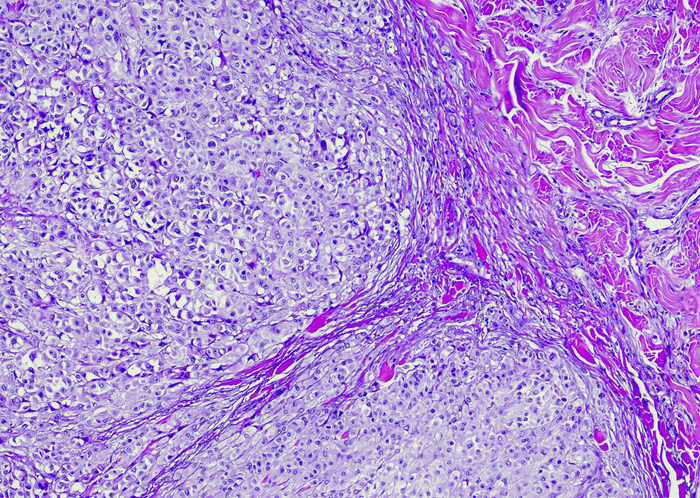

The U.S. Food and Drug Administration recently approved pexidartinib (Turalio™) for the treatment of advanced tenosynovial giant cell tumor (TGCT). The phase III ENLIVEN trial for which the approval was based found that this is the first systemic therapy to show a robust tumor response in TGCT with improved patient symptoms and functional outcomes. The study results were published in The Lancet.

Serious adverse events (AEs) occurred in eight (13%) patients in the pexidartinib group and one (2%) patient in the placebo group. Common AEs associated with pexidartinib were hair color changes (67%), fatigue (54%), aspartate aminotransferase increase (39%), nausea (38%), alanine aminotransferase increase (28%), and dysgeusia (25%). Three patients who received pexidartinib had aminotransferase elevations three or more times the upper limit of normal (ULN) with total bilirubin and alkaline phosphatase two or more times the ULN indicative of mixed or cholestatic hepatotoxicity; one of these lasted seven months and was confirmed by biopsy.